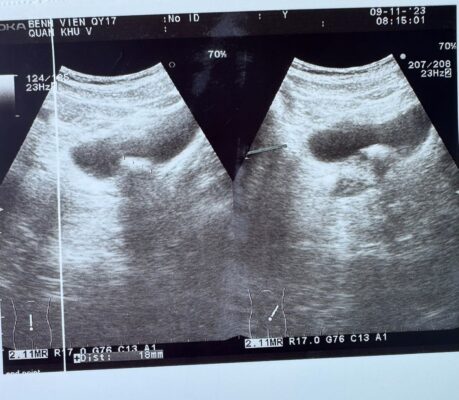

+ Siêu âm hệ tiết niệu: 2 thận bình thường. Hình ảnh khối tăng âm trong bàng quang, có bóng lưng, kích thước 18 x 10 mm.

Hình 1: Siêu âm bàng quang, hình ảnh nốt tăng âm trong bàng quang lệch trái